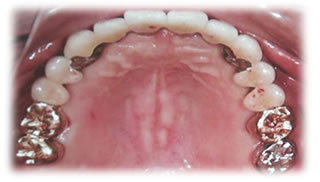

- 診断用模型上下の印象(歯型取り)

- マウスピースの作成

→基本的に上顎での作成